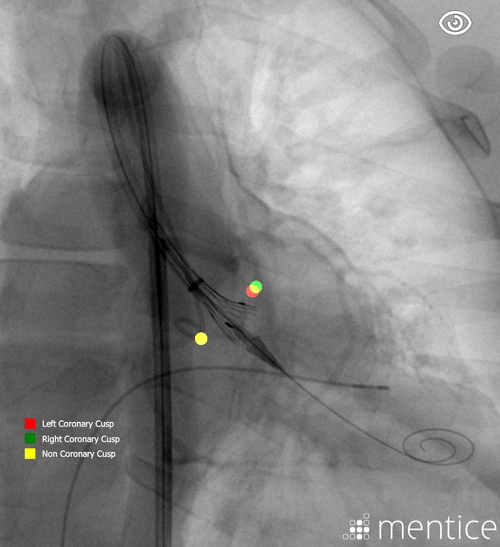

Mentice Aortic Valve Implantation is designed for interventional cardiologists and cardiac/cardiothoracic surgeons who wish to train on transcatheter aortic valve implantation/replacement (TAVI/TAVR). As TAVI volumes increase due to expanding reimbursement and its adoption for younger, low-risk patients, effective training becomes critical to ensure consistent outcomes. This module provides a safe, cost-effective platform for individual instruction or hospital-wide quality improvement programs.

With generic balloon and self-expandable valves, users can explore the nuances of different deployment techniques and adapt to the growing variety of valves on the market. Physicians can refine skills like the cusp overlap technique, deepen their understanding of anatomy, and prepare for the challenges of treating diverse patient profiles—all in a realistic and patient-free environment.

Learn how to accurately perform commissural alignment

Enhances anatomy understanding and deployment accuracy with augmented visualization